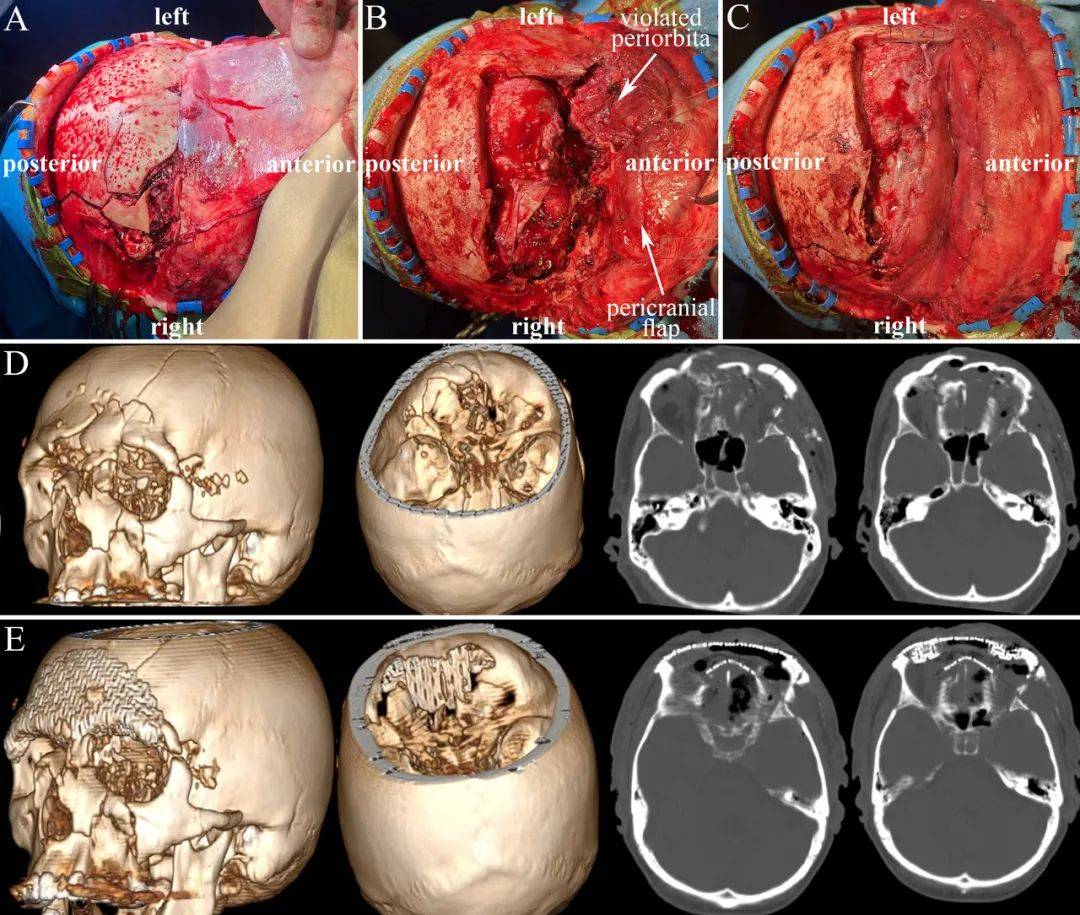

重型颅脑外伤常遗留的并发症和后遗症如下1并发症脑脊液瘘,大多数脑脊液瘘在一周左右会自行闭合,如超过两周需手术处理颈内动脉海绵窦瘘,指颅底骨折刺伤颈内动脉血管,患者出现波动性凸眼颅内杂音口鼻流血症状,需做介入和海绵窦手...